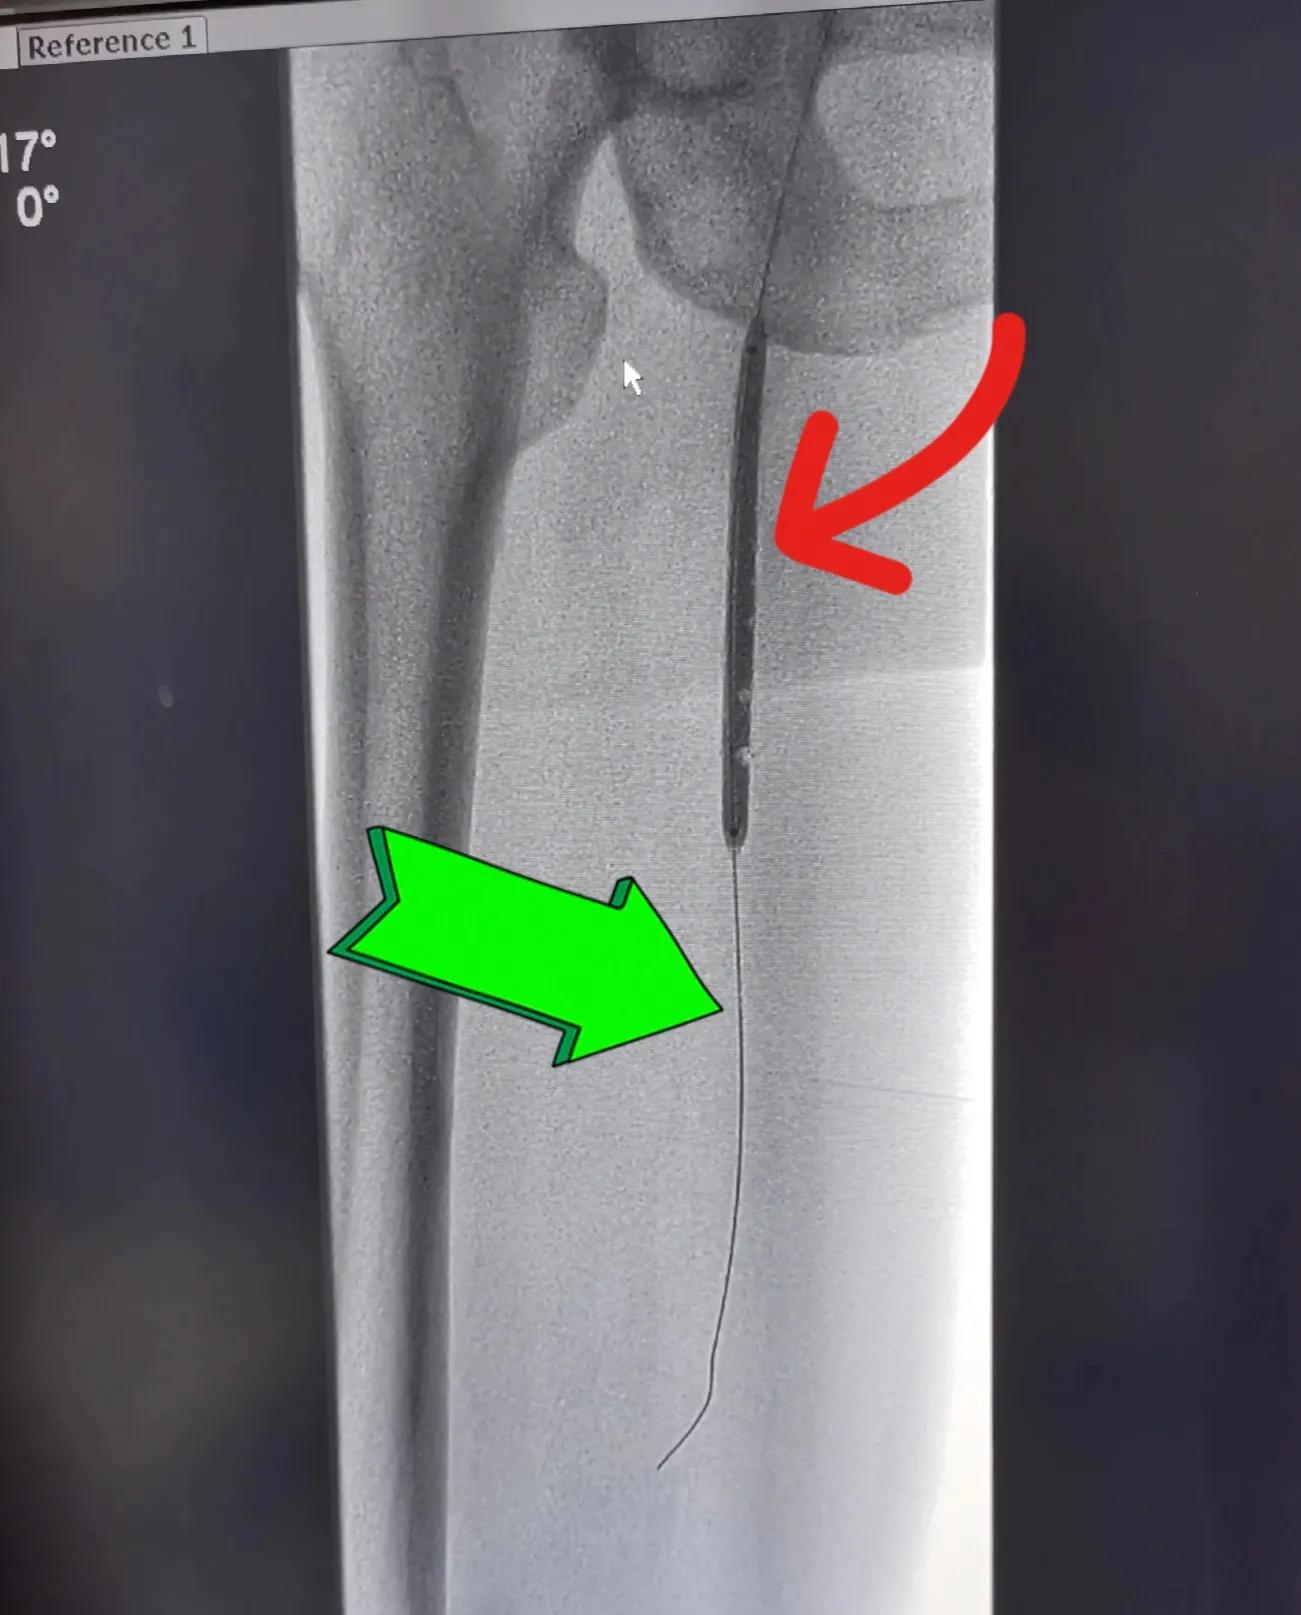

图一:红色箭头所指左侧股动脉狭窄,绿色箭头所指是介入医生把泥鳅导丝放入股功脉内,准备植入支架

图一至图五是2022年9月初浙江普陀医院(公立)骨科医生对退休教师李某某髂动脉,股动脉闭塞性动脉硬化进行介入治疗前后血管造影对比。显示血管内支架植入后血管形态非常好,患者出院后术后一个月观察,走路时下肢疼痛完全消失,间歇性跛行症状消失,两下肢功能完全恢复。